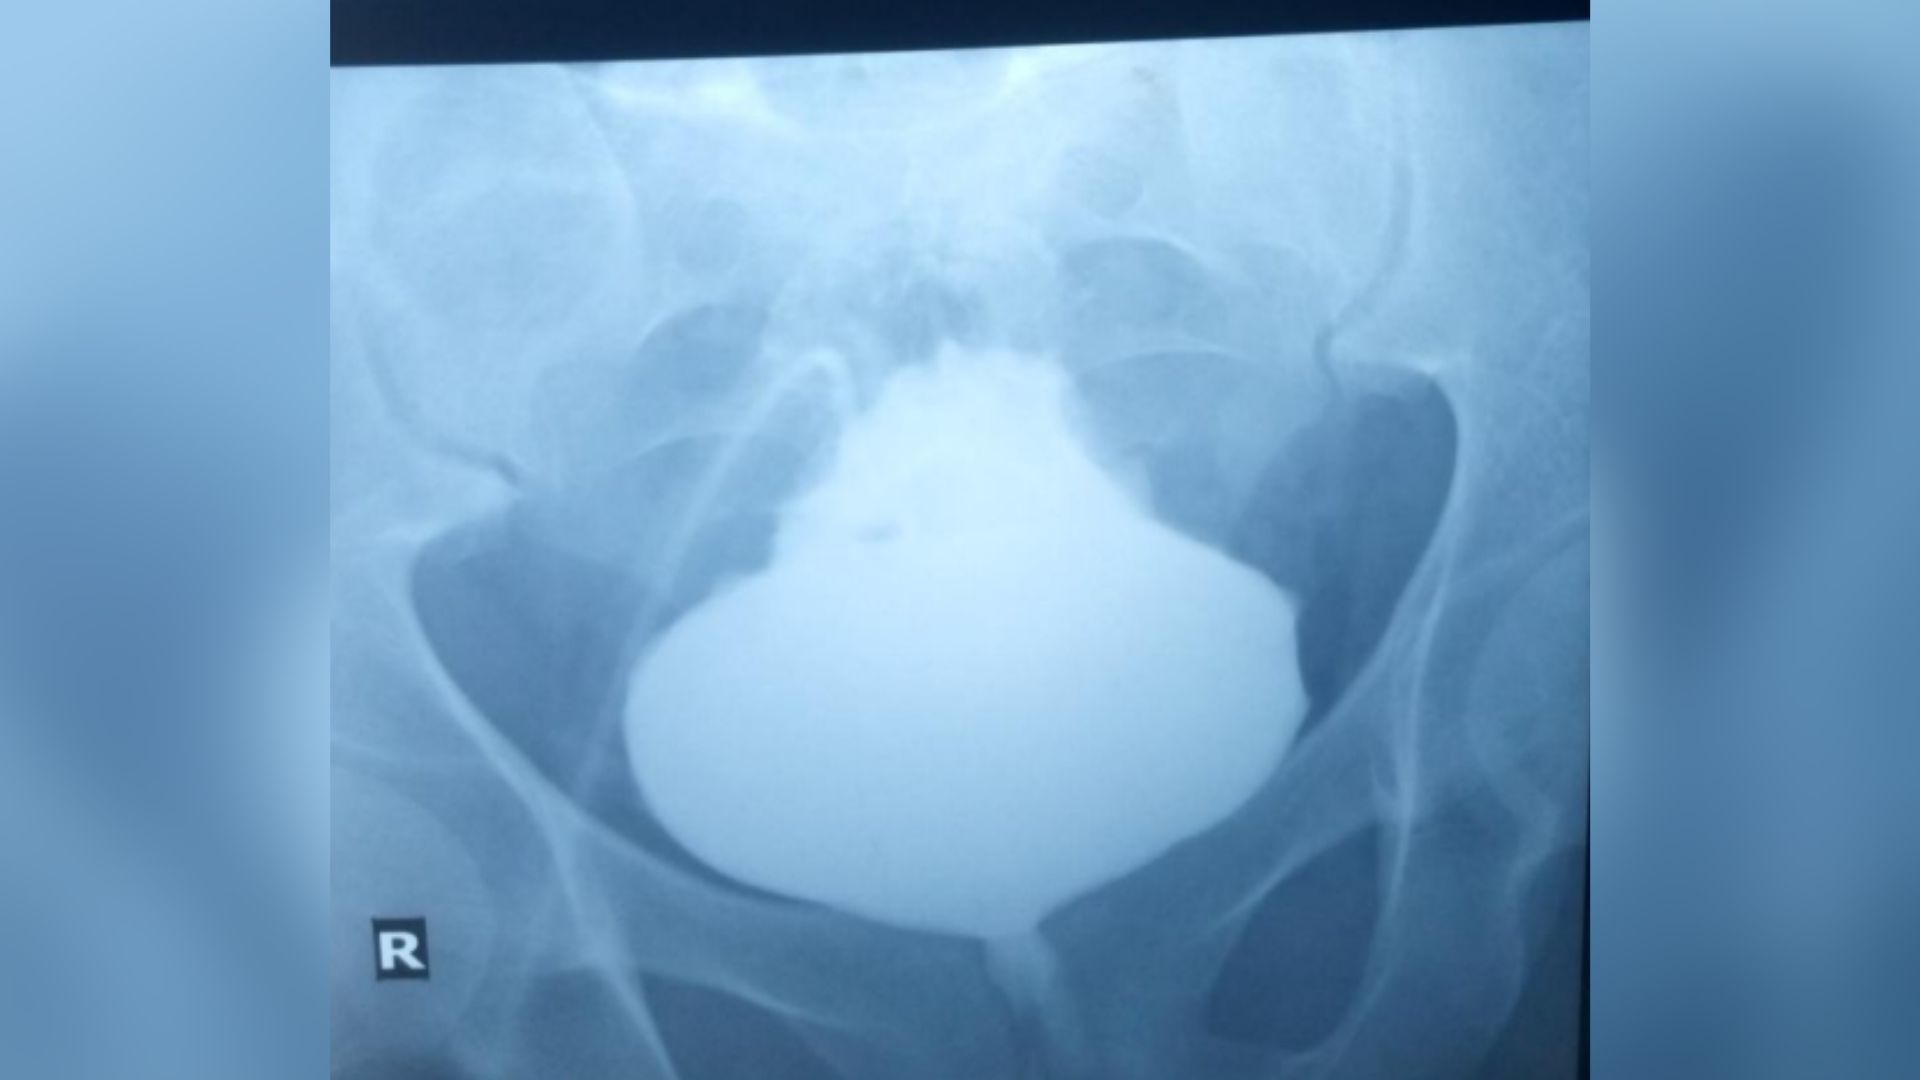

Doctors referred the patient to radiology and obtained a scan of the bladder to look for signs of such physical abnormalities. To visualize the bladder on the X-ray scan, the radiologist administered an X-ray sensitive dye through an abdominal catheter. This revealed that the base of the bladder was distended, leaving behind a pointed tip.

Diagnosis: This condition is known as a “Christmas tree” or “pinecone” bladder because of its appearance.

X-rays confirmed that urine was blocked from leaving the organ. However, a detailed examination of the bladder revealed that there was no problem with the organ itself, such as an obstructive mass or a bladder stone. This led doctors to think that the obstruction might be elsewhere.